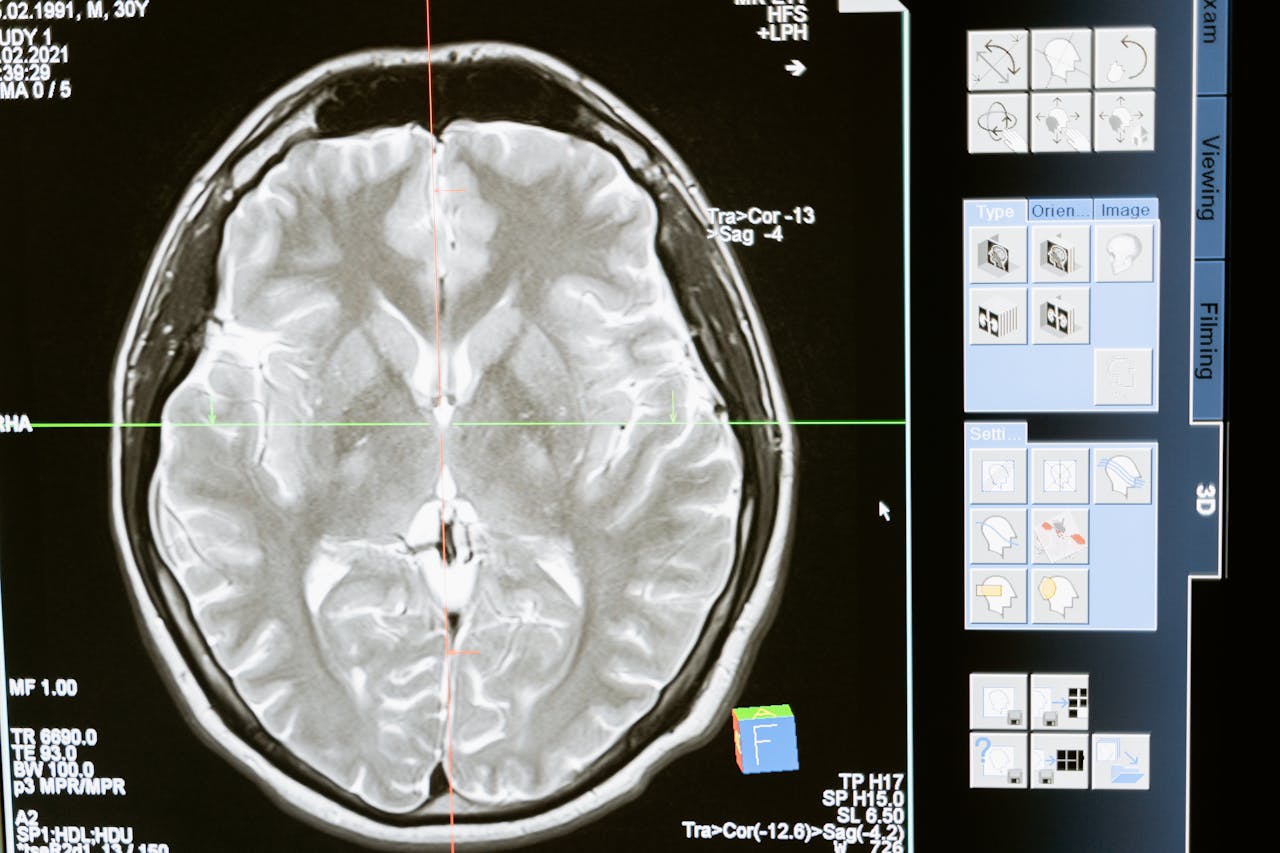

5.뇌혈관질환 (Stroke)

유형: 뇌출혈(혈관 파열), 뇌경색(혈관 막힘)

증상: 언어장애, 반신마비, 시야 흐림 등

골든타임: 증상 발생 3시간 이내 치료가 핵심

뇌혈관질환(뇌경색, 뇌출혈,혈관성치매 ) - 당신도 알지 못하면 어려움 겪습니다

뇌혈관질환 - 현실적인 이해와 대처1. 뇌혈관질환의 원인뇌혈관질환은 뇌로 가는 혈류에 문제가 생겨 발생하는 질환입니다뇌혈관질환은 하루아침에 발생하지 않습니다.대부분은 수년, 수십 년